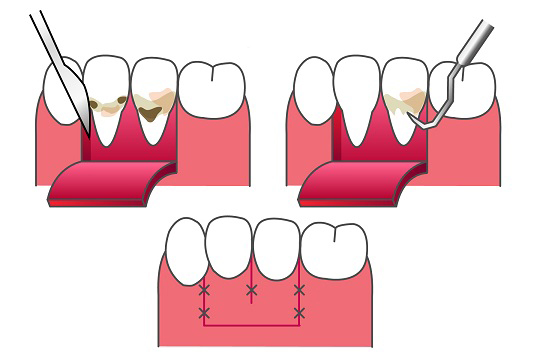

重度歯周病への挑戦:歯周外科治療(フラップ手術)

基本治療を行っても歯周ポケットが改善しない場合、通常の器具では届かない深い場所に細菌が残っている可能性があります。

歯周外科治療(フラップ手術)とは、歯ぐきをわずかに切開し、直接目で見える状態で、歯の根の深い部分にこびりついた汚れを完璧に取り除く手術です。

手探りの治療ではなく、「直接見て」処置を行うため、確実性が格段に上がります。口腔外科の経験が豊富な院長が行うため、手術は短時間で、痛みや腫れを最小限に抑えて進めることができます。